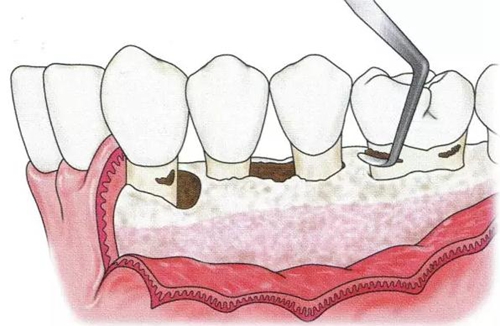

肉芽組織去除后,出血就可以得到控制,殘存牙結(jié)石的附著狀態(tài)可以更清楚,骨吸收狀態(tài)和骨缺損狀態(tài)的有無也能夠明確知道。另外,術(shù)后治愈效果也會良好。清除牙結(jié)石時,注意不要有殘留(圖15-1~3)。

▼圖15-1  顯示牙齦翻瓣進行齦下刮治和根面平整的圖像。不良肉芽組織的去除和包含SC/RP在內(nèi)的清創(chuàng)處理決定了牙周外科處理結(jié)果是否良好。

18.jpg